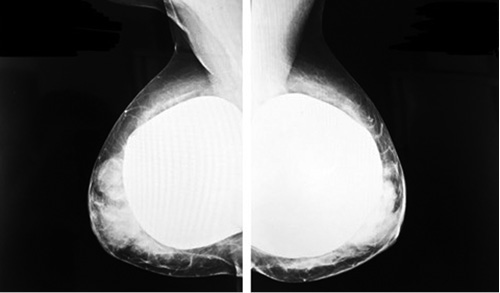

1. Fig. 1. Mammography of 2017 after subtotal reduction plastic surgery with prosthetics. | |